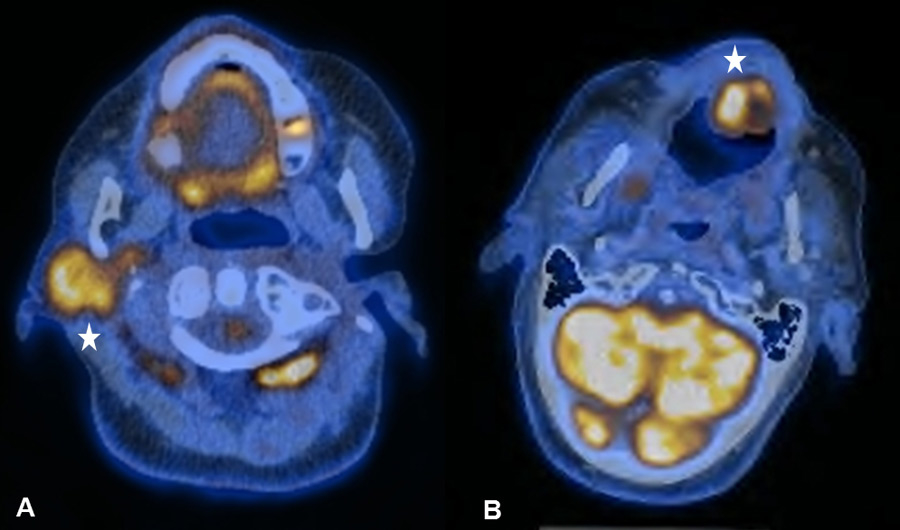

Figure 1

(A) Bilateral physiological uptake in the palatine tonsils in a 83-year old patient with a past medical history of a floor of nose melanoma. (B) Symmetric increased uptake in the muscles of mastication in 71-year old patient treated for tonsillar carcinoma.

It is known that PET-CT is more accurate in detecting HNC recurrence than conventional physical examinations alone and that therefore negative periodic clinical examinations may be complemented by FDG PET-CT [8, 15]. As expected, we observed PET-CT to be a well-established ruling-out test at the expense of a decreased positive predictive value and specificity [7–9]. However, interpretation of indistinct FDG-positive findings remains challenging because of a high number of false-positive lesions and the necessity for potentially unnecessary and invasive diagnostic investigations. As in previous studies, we found typical foci of increased FDG uptake [16, 17]. The pharyngeal mucosa frequently causes physiological FDG uptake, hence the interpretation is usually unproblematic as long as the uptake is located superficially along the mucosal plane in linear configuration [18]. The palatine tonsils and other lymphatic structures of the Waldeyer’s ring typically exhibit FDG uptake, which most likely reflects a so-called “physiological inflammation” of the lymphatic tissue due to confrontation with antigens [18, 19] (fig. 1A). Furthermore, muscles of mastication and intrinsic tongue muscles were shown to be highly sensitive to exogenous confounders such as chewing gum during examination and therefore a good quality of PET-CT/MRI clearly depends on the compliance of the patient [20, 21] (fig. 1B). With regard to the floor of mouth (FOM) muscles, a recent study investigating the effect of a supine versus a sitting position on physiological FDG accumulation, did not find any alterations and concluded that there is no trick to avoid or reduce this kind of disturbing FDG uptake [22]. The correlation between muscular activity and increased FDG uptake was also shown for the larynx, since talking can cause FDG uptake in the muscles of phonation as well as in the vocal cords [18, 23]. In terms of FDG uptake in the salivary glands, the parotid, submandibular and sublingual glands may all reveal mild to moderate symmetric or asymmetric uptake, although these findings underlie a marked inter-individual variability [16, 17]. As there is a close relationship between reduction in FDG uptake into the salivary glands and increasing doses of RT, we found five patients with asymmetric salivary gland FDG uptake due to surgical treatment and RT to the contralateral side [24] (fig. 2A). Similarly, we observed four patients with asymmetric FDG uptake in the tongue and FOM as a consequence of muscular imbalance due to contralateral surgical treatment (fig. 2B). Another well-known phenomenon is the increased FDG uptake in the contralateral vocal cord if a recurrent laryngeal nerve palsy is present (fig. 3AB).